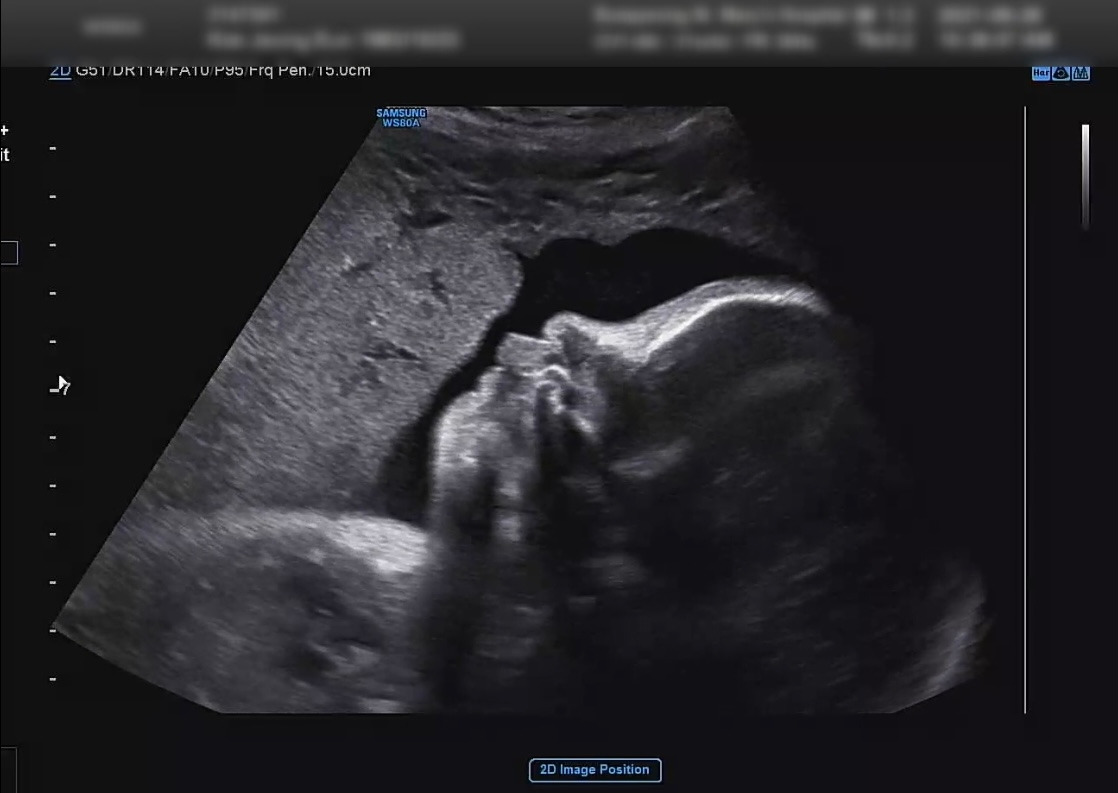

정기검진 날, 지난주 응급실을 다녀온 이후로 출혈은 없었지만 그래도 뭔가 불안한 마음과 괜찮겠지라는 조심스런 확신과 쌩쌩이가 그동안 많이 컸을까 하는 궁금한 마음으로 병원에 갔다.

초음파실 3개의 방 중 가운데 방에서 초음파를 봤는데 그 방은 3D 입체 초음파 기계가 있는곳이라서 혹시 얼굴을 볼 수 있을까 하는 기대를 했다.

2주전까지만 해도 머리가 위로 가 있었는데 다행히 아래로 내려가 있다고 했고 심장부터 공팥, 팔다리 뼈, 척추 등을 찬찬히 살펴보고는 바로 보호자 오셨냐고 물어봤다.

주호가 들어왔고, 초음파 쌤은 좀 더 자세히 설명해주면서 엉덩이, 머리, 손, 발, 척추를 보여주었지만 아무래도 얼굴은 안 보여줄 것 같아서 '혹시 얼굴 볼 수 있어요?'라고 물어봤더니 '잘 안보일 것 같은데~' 라면서 찾아봐주었다. 주호도 옆에서 '저희가 아직 얼굴을 한번도 못봤어요.' 라고 하면서 아가 얼굴이 넘 보고싶다는 분위기를 뿜뿜해 주었더니 초음파 쌤이 좀 더 열심히 이쪽 저쪽 봐주었다.

얼마 안되어서 얼굴이 보였다!

쌩쌩이가 초음파 볼 때마다 팔로 X자를 만들어 얼굴을 가리고 있더니 이번에는 얼굴을 보여주었다.

쌩쌩이는 다행히 그 동안 잘 커주어서 이제 1.6kg이 되었고 정상적인 범위에서 건강하게 자라고 있다고 한다.

쌩쌩이(210928_01).jpg